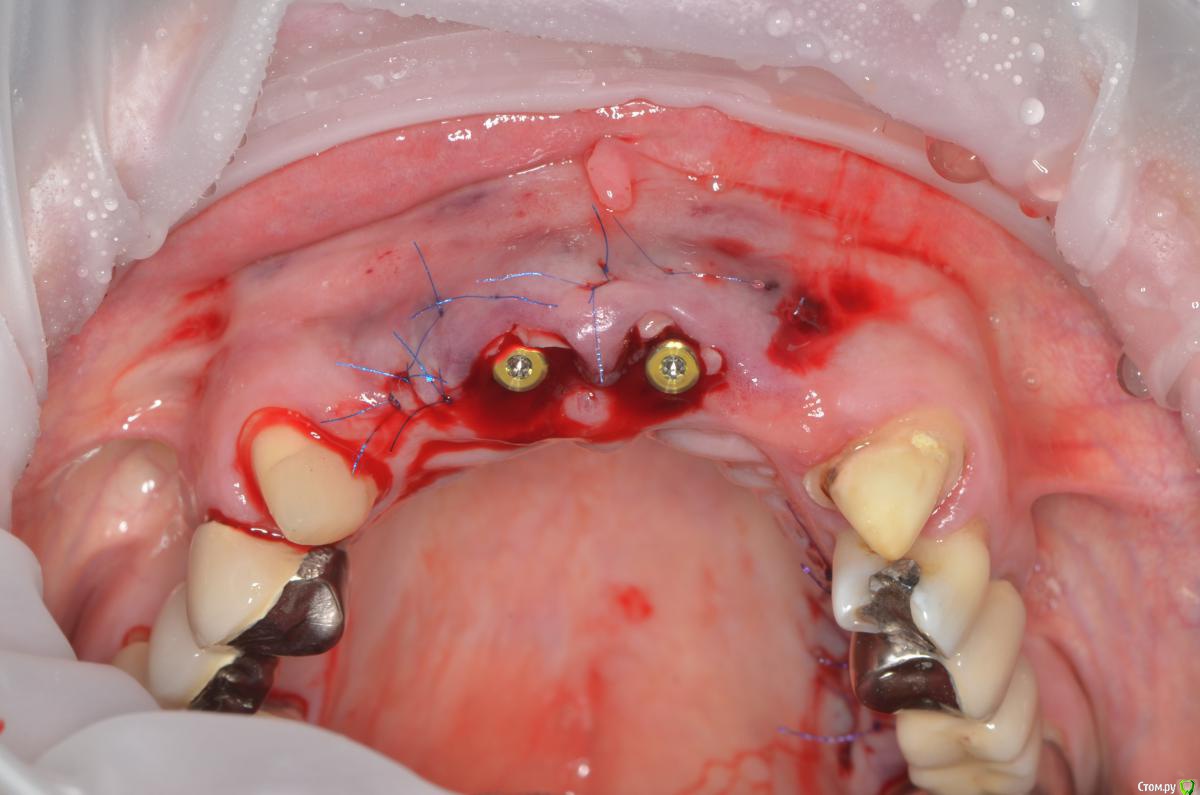

gangsta85 Опубликовано 27 сентября, 2016 Поделиться Опубликовано 27 сентября, 2016 Здравствуйте, уважаемые коллеги.Помогите пожалуйста разобраться.Центральные резцы в\ч были удалены и установлено 2 имплантата с пластикой десны, 12,22 отсутствуют в области 12 трансплантация слизистого лоскута.В тот же день изготовлены времянки по ключу с ваксапа. профиль трансгингивальной части сделан максимально под размер постоянной реставрации. 12,22 овоиды плотно прилегающие к десне.Вопросы:- Можно ли изготовить времянки сразу по форме максимально похожей на будущие реставраций и свести к минимуму коррекции профиля десны?- можно ли сделать надрез в области 22 и максимально погрузить в десну овоид 22, насколько плотно можно прижать овоид 11 в области слизистого трансплантата?- можно ли в такой ситуации добиться формирования десневых сосочков в области 12,22?-через какое время можно снять времянки для коррекции?- постоянная реставрация через 4 месяца? Что если снять слепок в день операции в лаборатории отфрезеровать времянки и установить через 1-2 дня , удастся ли в программе отмоделировать правильный профиль десны и овоиды? Как бы вы предпочли сделать времянки на CAD\CAM или в ручную? Ссылка на комментарий